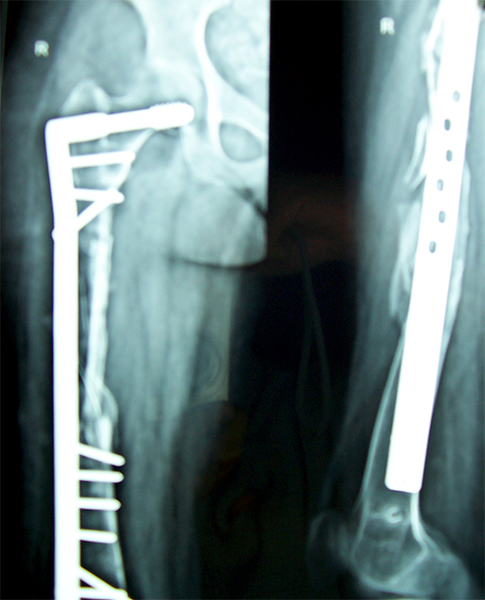

Case:5 Ewing sarcoma with implant failure

Breakage of Nail

Refixation with Angle Bladed Plate and Sever Graft